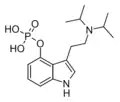

| 4-PO-DiPT | artificial | 4-OPO3H2 | CH(CH3)2 | CH(CH3)2 | 4-phosphoryloxy-N,N-diisopropyltryptamine | 1373882-09-7 |